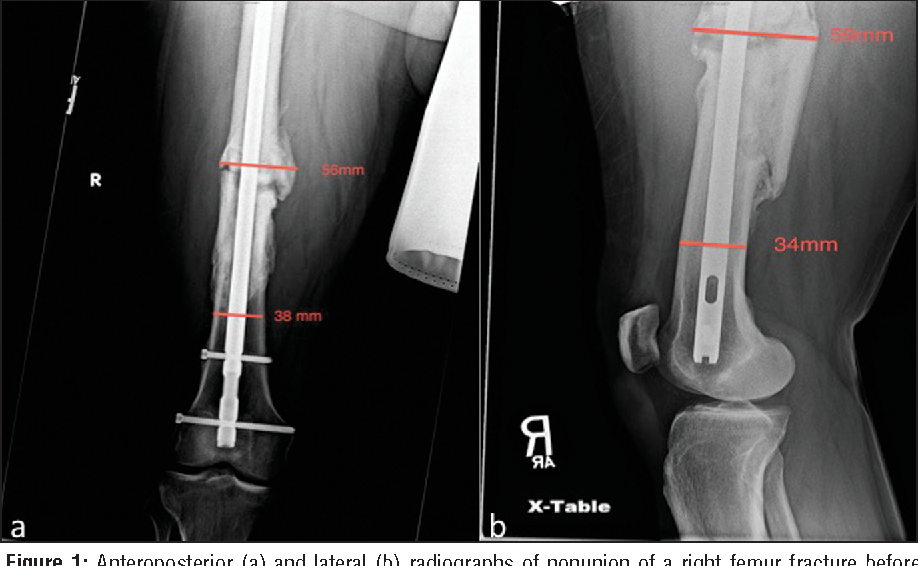

아래와 같은 nonunion에서 dynamization으로 골유합을 유도할 수 있습니다.